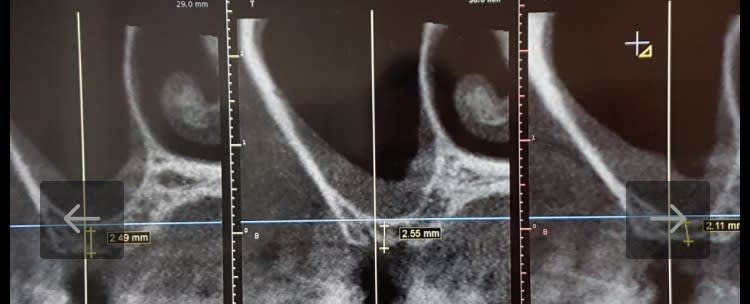

La procédure est simple, mais varie selon la hauteur sous sinusienne, à savoir plus ou moins de 4 MM. Avec 2,5 mm, j'ai foré sur 1 mm avec le pointeur, puis passage du foret 3.0 mm en mode reverse à 900 tr/min jusqu'à la corticale. Ensuite une fois cette dernière passée, on repousse la membrane toujours en mode reverse en veillant à ne jamais faire pénétrer le foret de plus de 3 mm dans le sinus.

J'ai testé la membrane avec ma sonde jauge, tout allait bien. Puis comblement à l'OSTEON II de Dentium en seringue, c'est plus pratique. Chez Versah, ils utilisent le novabone pur le côté pratique de l'embout. Après, je pense que le type de matériaux compte peu, il sert juste d'échaffaudage. Et je pense qu'un matériau à résorption lente type Béta TCP est plus adapté.

J'insère donc la xénogreffe, puis elle est poussée avec mon foret de 3 mm toujours en mode reverse à 100 trs/min et 50 N de couple. Enfin insertion de l'implant. EN moyenne j'obtiens 40 à 50 N. vis de couverture et attente de 6 mois. Je vais mettre les radios.

Ce système est révolutionnaire je trouve, aucune suite pour le patient, on obtient une osséodensification et une légère expansion également. J'ai récemment lu une étude attaquant ce système qu serait source de microfracture osseuse et d'ischémie. Après analyse, les cas concernaient des implants mandibulaires et des implants BICON.... Forcément on est hors indication:)